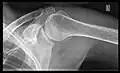

X-ray

Projectional radiography views of the shoulder include:

- AP-projection 40° posterior oblique after Grashey

The body has to be rotated about 30 to 45 degrees towards the shoulder to be imaged, and the standing or sitting patient lets the arm hang. This method reveals the joint gap and the vertical alignment towards the socket.[26]

- Transaxillary projection

The arm should be abducted 80 to 100 degrees. This method reveals:[26]

- The horizontal alignment of the humerus head in respect to the socket and the lateral clavicle in respect to the acromion

- Lesions of the anterior and posterior socket border, or of the tuberculum minus

- The eventual non-closure of the acromial apophysis

- The coraco-humeral interval

- Y-projection

The lateral contour of the shoulder should be positioned in front of the film in a way that the longitudinal axis of the scapula continues parallel to the path of the rays. This method reveals:[26]

- The horizontal centralization of the humerus head and socket

- The osseous margins of the coraco-acromial arch and hence the supraspinatus outlet canal

- The shape of the acromion

This projection has a low tolerance for errors and, accordingly, needs proper execution.[26] The Y-projection can be traced back to Wijnblath’s 1933 published cavitas-en-face projection.[27]

-

CR. shoulay film. -

Transaxillary conventional radiography -

Y-projection conventional radiography